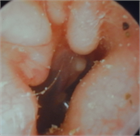

1. 耳閉感を伴う疾患は様々で、患者の訴えも「耳がつまる」以外に「耳がふさがった感じ」「耳の違和感」「音が反響する」「水が入ったような」など多様であるため、初診時の丁寧な問診が重要である(推奨度1)

1. 異物など除去により症状が消失するケースを除き、聴覚検査は診断に必須である(推奨度1)

1. 耳閉感を訴えている症例の中には、耳以外の疾患が原因の場合がある。特に脳血管疾患、腫瘍性疾患など生命予後を左右する鑑別疾患の可能性を想定した場合には、積極的に画像検査を施行する(推奨度1)